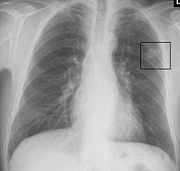

Use of medical imaging to search for cancer in people without clear symptoms is similarly marred with problems. There is a significant risk of detection of what has been recently called an incidentaloma - a benign lesion that may be interpreted as a malignancy and be subjected to potentially dangerous investigations. Recent studies of CT scan-based screening for lung cancer in smokers have had equivocal results, and systematic screening is not recommended as of July 2007. Randomized clinical trials of plain-film chest X-rays to screen for lung cancer in smokers have shown no benefit for this approach.